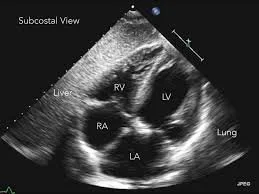

ECHO:

• Non Stress Echos